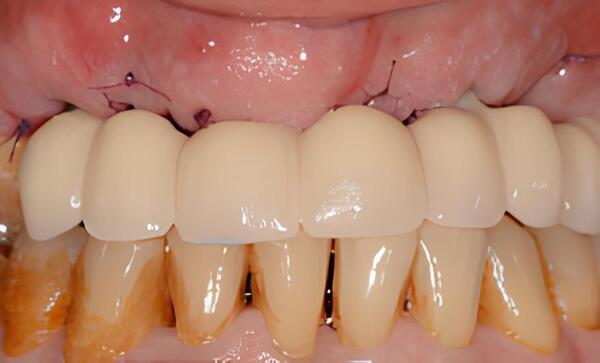

IMPLANTOLOGIE : LES BRIDGES FIXES COMPLETS MANDIBULAIRES